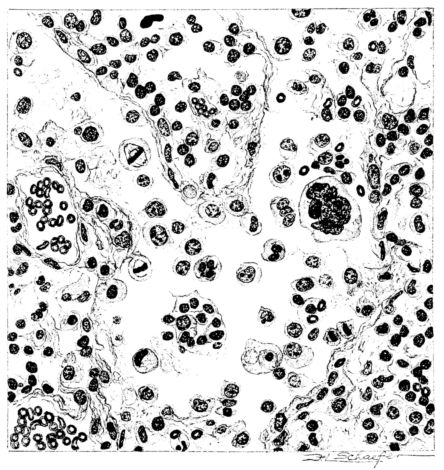

FIG. II. AUTOPSY NO. 98. DRAWING OF A SECTION THROUGH A TRACHEA SHOWING NECROTIZING HEMORRHAGIC INFLAMMATORY PROCESS OF THE MUCOSA.

The changes are less marked, perhaps, in the trachea than in its finer ramifications. The mucosa is constantly more or less destroyed and large areas, usually focal, are entirely devoid of their epithelial covering. This is replaced by a sparse exudate, composed largely of red blood cells, mucus, a small amount of fibrin, and nuclear fragments (Fig. II). It may dip into the submucosa for a short distance, but usually these indentures are associated with the ducts of the mucous glands into which the inflammatory reaction extends. A more striking feature than the exudate, however, is the edema and the congestion of the submucosa. The loose areolar tissue of the submucosa is spread widely apart, and throughout it distended blood vessels are very conspicuous. Occasionally such a vessel is broken and actual hemorrhage appears in the submucosa. Occasionally, too, the inflammation extends down the duct to the mucous gland itself, and here, also, aplastic inflammatory reaction is evident, inasmuch as the acini now stain intensely red with the cells undifferentiated from each other and specked here and there by broken remains of the dead nuclei (Fig. III). After the disease has continued for a short period, even at the end of five or six days, some regeneration of the epithelial lining may be seen (3) (Fig. IV). But despite this, the acute picture persists, and there goes on, side by side, an attempted repair characterized by epithelial regeneration and the same evidence of acute change. Since the lesion is essentially a superficial one, scars or contractures of any extent are not encountered in the trachea, even in examples of the disease that have ended fatally only after many weeks.[4]